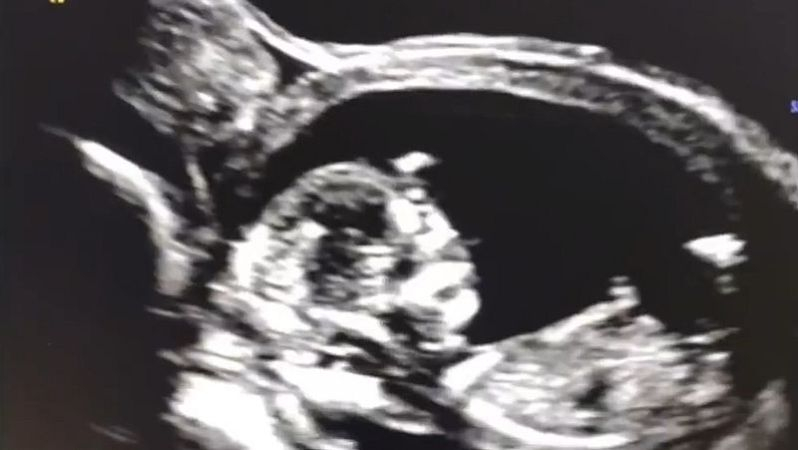

Die Frau in folgendem Video wurde während der Schwangerschaft mit dem Gen-Medikament "geimpft". Die zweite Dosis erhält sie am 8. Dezember 2021. Zu diesem Zeitpunkt ist sie in der 12. Schwangerschaftswoche. Am 4. Januar, als sie zum nächsten Ultraschall geht, ist ihr Sohn tot. Die Messungen ergeben, dass er unmittelbar nach der Gen-Behandlung der Mutter gestorben sein muss, weil er nach der 12. Woche nicht mehr gewachsen ist...